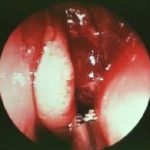

✔ Sialoendoskopi: Küçük kamera ile doğrudan kanal içine bakılarak taşın yerinin tespit edilmesi ve tedavide kullanılması için de tercih edilebilir.

Sialoendoskopi: Küçük bir kamera ve aletlerle taşın kanaldan çıkarılması

Sialoendoskopi (hem tanı hem tedavi)